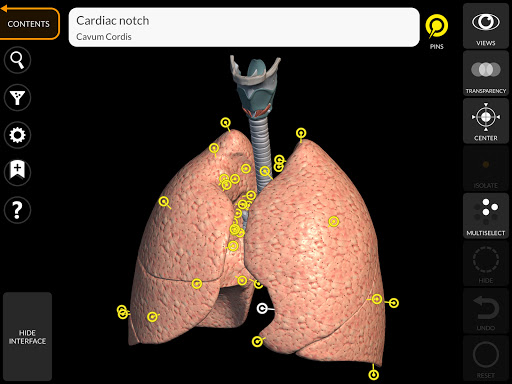

"Anatomía - Atlas 3D" permite estudiar la anatomía humana de forma fácil e interactiva.

A través de una interfaz sencilla e intuitiva es posible observar cada estructura anatómica desde cualquier ángulo.

Los modelos anatómicos 3D son especialmente detallados y con texturas de hasta una resolución de 4k.

La subdivisión por regiones y las vistas predefinidas facilitan la observación y el estudio de partes individuales o grupos de sistemas y las relaciones entre los diferentes órganos.

nervioso • Sistema respiratorio • Sistema digestivo • Sistema urogenital (masculino y femenino) • Sistema endocrino • Sistema linfático • Sistema ocular y auditivo CARACTERÍSTICAS • Interfaz sencilla e intuitiva • Rotar y hacer zoom en cada modelo en el espacio 3D • Opción para ocultar o aislar uno o varios modelos seleccionados • Filtro para ocultar o mostrar cada sistema • Función de búsqueda para encontrar fácilmente cada parte anatómica • Función de marcador para guardar vistas personalizadas • Rotación inteligente que mueve el centro de rotación automáticamente • Función de transparencia • Visualización de músculos a través de niveles de capas desde las superficiales hasta las más profundas • Al seleccionar un modelo o un pin, aparece el término anatómico relacionado • Descripción de los músculos: origen, inserción, inervación y acción • Mostrar/ocultar interfaz de usuario (muy útil con pantallas pequeñas) MULTILINGÜE • Los términos anatómicos y la interfaz de usuario están disponibles en 11 idiomas: latín, inglés, francés, alemán, italiano, portugués, turco, ruso, español, Chino, japonés y coreano • Los términos anatómicos se pueden mostrar en dos idiomas simultáneamente REQUISITOS DEL SISTEMA • Android 8.0 o posterior, dispositivos con al menos 3 GB de RAM Reversi

• Sistema respiratorio